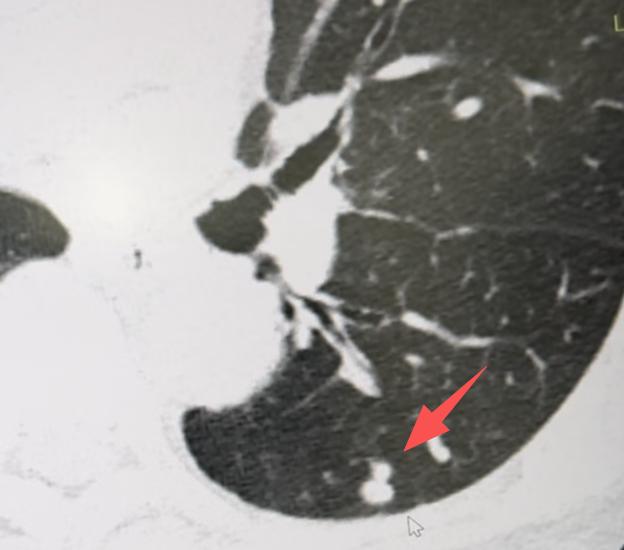

朋友们!别一看到“肺结节”几个字就紧张!其实在检查中发现肺结节非常普遍,绝大多数都和炎症有关,真正由肿瘤引起的情况极少。 肺结节本身是一个影像上的描述,不代表就是不好的东西。所以查出肺结节后,先别急着做手术,不妨给自己一点观察的时间。 一般来说,肺结节可能有以下几种情况: 1、急性炎症引起的结节,可以用消炎药。比如最近正好有发烧、咳嗽,同时查出了肺结节,这很可能是呼吸道感染导致的。 按照医生建议吃一段时间的消炎药,把细菌控制住,结节很可能就慢慢消失了。 这种炎症期的结节,在CT上常常表现为边缘模糊、不太规则,有时候像一小片云雾。 2、有些炎症结节,不用药也可能自己消失。当我们免疫力下降,或者接触的细菌比较多时,肺部可能出现局部炎症。 但如果注意休息、提高抵抗力,身体里的免疫细胞是有能力把这些细菌清除掉的,结节也就随之消散了。 3、还有一些结节是炎症吸收后留下的“痕迹”,就像皮肤受伤后结的疤,已经稳定了。这种陈旧性结节,吃消炎药通常也消不掉,重点就不是用药,而是定期复查、观察变化。 所以,查出肺结节先别慌,大多数情况下它并不可怕。平时注意保持健康生活习惯——吃好、睡好、心情放松,让免疫力维持在良好状态,就是对我们肺最好的保护。[玫瑰][谢谢]胸外科乔贵宾医生肺结节[超话]